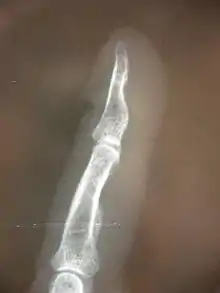

La luxation articulaire est définie comme un déplacement évident entre deux os. La subluxation est un processus plus discret de déplacement entre deux articulations, pas nécessairement décelé sur une radiographie ou une imagerie à résonance magnétique.

Subluxations des membres périphériques

Celles-ci suivent également la règle précitée de subluxation articulaire avec des conséquences neurologiques dans certains cas. Néanmoins, les conséquences de déplacements osseux sur les parties périphériques du corps sont souvent beaucoup plus prévisibles en termes de conséquences sur les fonctions nerveuses, tant au niveau moteur qu'au niveau sensoriel, ou encore pour ce qui est des fonctions végétatives (épidermiques et circulatoires notamment)